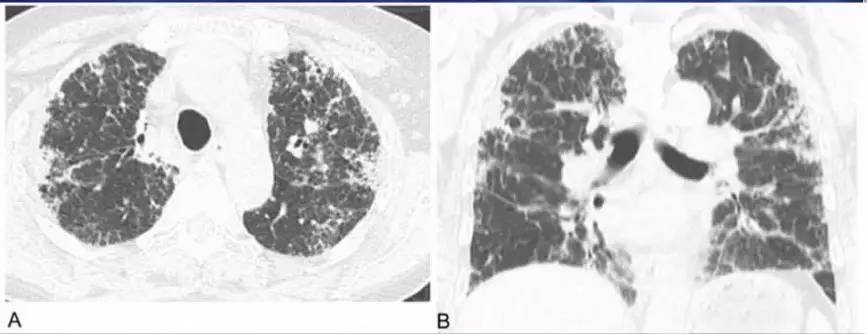

急性期胸部CT表现为两肺弥漫的磨玻璃密度影或广泛的实变影,主要分布在中下肺(如图7)。

图 7:OHP急性期胸部CT表现

2.慢性型主要表现为逐渐加重的呼吸困难,容易疲劳,体重减轻,晚期可出现呼吸衰竭,肺心病体征。

慢性期胸部CT表现为:两肺内不规则的线样、网状、或蜂窝状阴影结节影,靠近胸膜分布局部有磨玻璃样改变,并可见牵张性支气管扩张(图8)。

图 8: OHP慢性期胸部CT表现